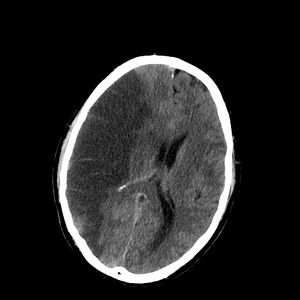

CT scan slice of the brain showing a right-hemispheric ischemic stroke (الجانب الأيسر من الصورة).